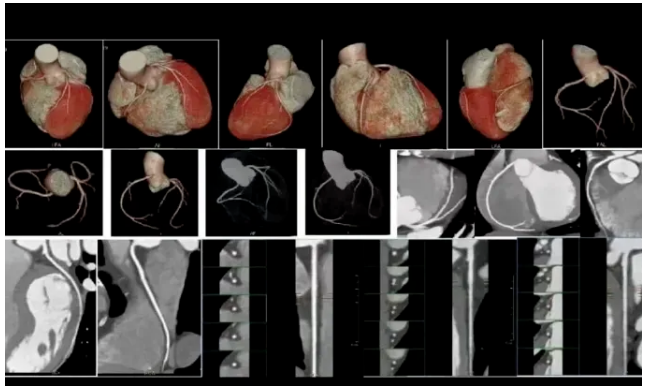

冠状动脉CTA是一种无创、快速、准确的检查。它就像给心脏血管做一次高清“立体摄像”,能清晰显示冠状动脉是否存在狭窄、钙化或斑块,以及斑块的性质(稳定或不稳定),直接评估冠心病风险。对于有胸闷、胸痛症状,或有高血压、糖尿病、高血脂、吸烟、心脑血管疾病家族史等高危人群而言,这项检查具有不可替代的重要价值。

洛阳白马医院引进的双源CT,是开展心脏冠状动脉CTA检查的先进设备。它配备两套X射线源与探测器系统,扫描速度极快,可在一次心跳内完成心脏高清成像,有效规避因心跳、呼吸产生的运动伪影。尤其针对心率较快或心律不齐的患者,双源CT也能获取清晰、可靠的图像,大幅提升检查的成功率与诊断准确性。